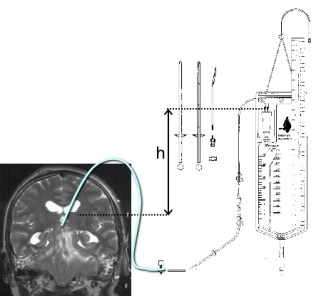

DVE : elle est basée sur le principe des vases communicants ; la hauteur h correspond à la pression d’ouverture en cm H2O (celle que le liquide doit vaincre pour s’écouler dans la poche), reflet de la pression intracrânienne la dérivation ventriculaire externe (DVE) : elle a un but à la fois thérapeutique (drainage) et diagnostique (aspect du liquide, pression d’ouverture), pour le drainage de durée courte (quelques jours à quelques semaines maximum) d’un liquide hémorragique ou infecté, ou comme sécurité après une chirurgie (tumeur ventriculaire, révision de valve compliquée). elle comporte un risque important de contamination bactérienne et ne peut donc être gardée plus d’une ou 2 semaines en général.